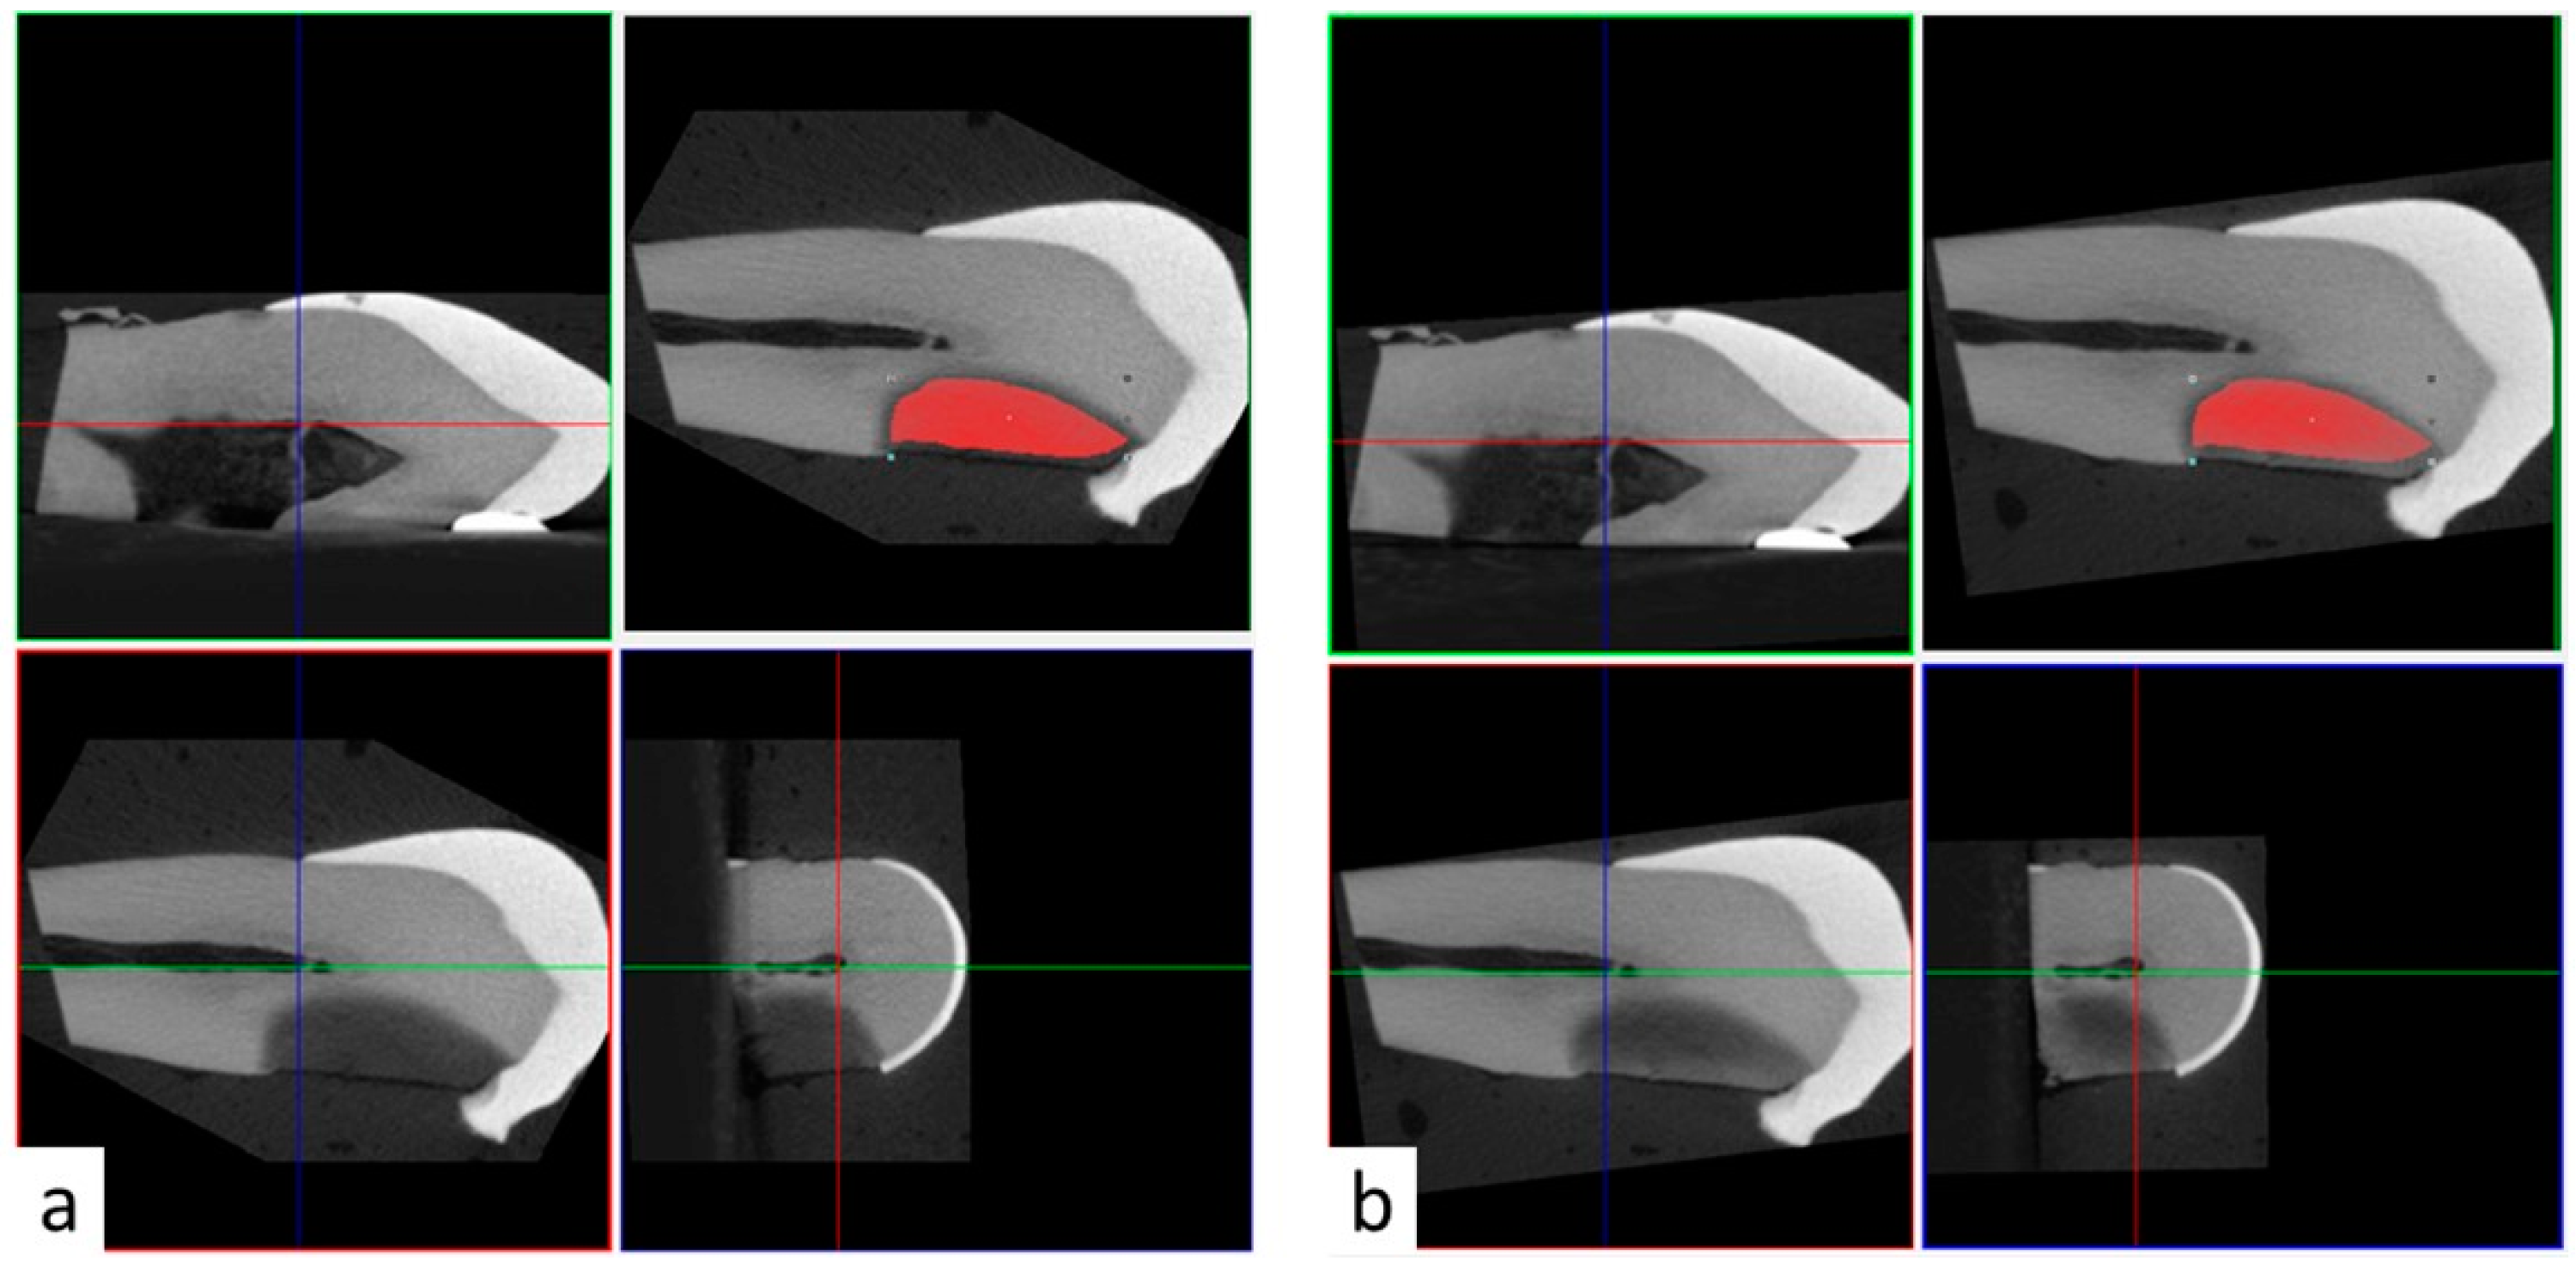

All teeth samples were imaged in air settings using micro-CT (SkyScan 1172; Bruker, Kontich, Belgium). Images were acquired using 11-Mp digital detector. Samples were scanned with 70 KV, 142 microamperes, 12 micron resolution, 0.4 rotational step and 1 mm aluminum filter. Samples were scanned preoperatively before SDF application, after SDF application, and after rinsing with 15 mL of water. Samples in Group 2 were also scanned after PI application. Three-dimensional reconstructed images were superimposed using the 3D coregistration function in DataViwer software. Briefly, the pre-operative reconstructed images served as reference images and stayed stationary. Post-operative reconstructed images (target images) were repositioned and registered in three dimensions over the reference images (Figure 1). As a result, it was possible to transfer the same region of interest (ROI) from the pre-operative reference images to the post-operative target images (Figure 1). The ROI was selected based on the radiopacity of the carious lesion in the preoperative 3D reconstructions using the thresholding function based on 0–255 greyscale units. The upper and lower threshold limits were set to allow clear distinction between the radiopacity of the carious lesion and the surrounding intact dentin, and between the radiopacity of the carious lesion and the surrounding wet gauze, respectively. These parameters were relatively consistent among samples with the upper limit ranging between 95–115 greyscale unit, and the lower limit ranging between 40–55 greyscale unit.

Figure 1. Three dimensional coregistration of reconstructed 3D images using DataViewer software. (a) Preoperative micro-CT images showing the region of interest (red outline) adapted to the carious lesion. (b) Coregistered 3D micro-CT images after application of a radiopaque material (e.g., potassium iodine) with the same region of interest transferred from preoperative to post-operative images.

Application of SDF alone resulted in dark staining on all teeth in Group 1. However, mild or no stain was noted in all carious lesions treated with SDF + PI in Group 2 (Figure 1).